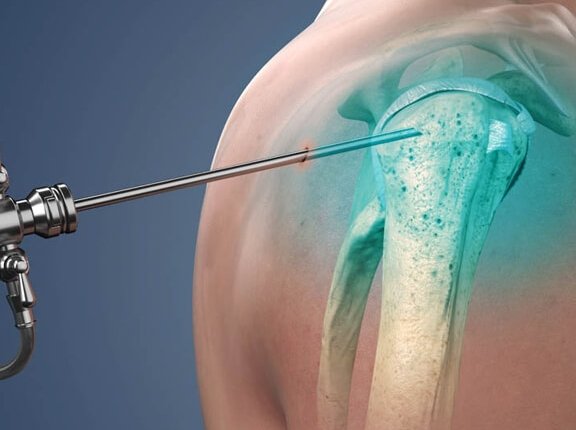

Dr. Shiva Shankaran GB is a senior specialist surgeon in knee and shoulder surgeries. He specializes in Sports injury, Arthroscopy, and Joint Replacement Surgeries. His journey is marked by a commitment to excellence and a relentless pursuit of knowledge. Physical Remedy and drugs are the first non-surgical options we look into when treating common pain, but if surgery is eventually necessary, we’ll give you the best treatment possible to help you return to your diurnal conditioning as soon as possible.

Arthroscopic & Replacement Surgeries